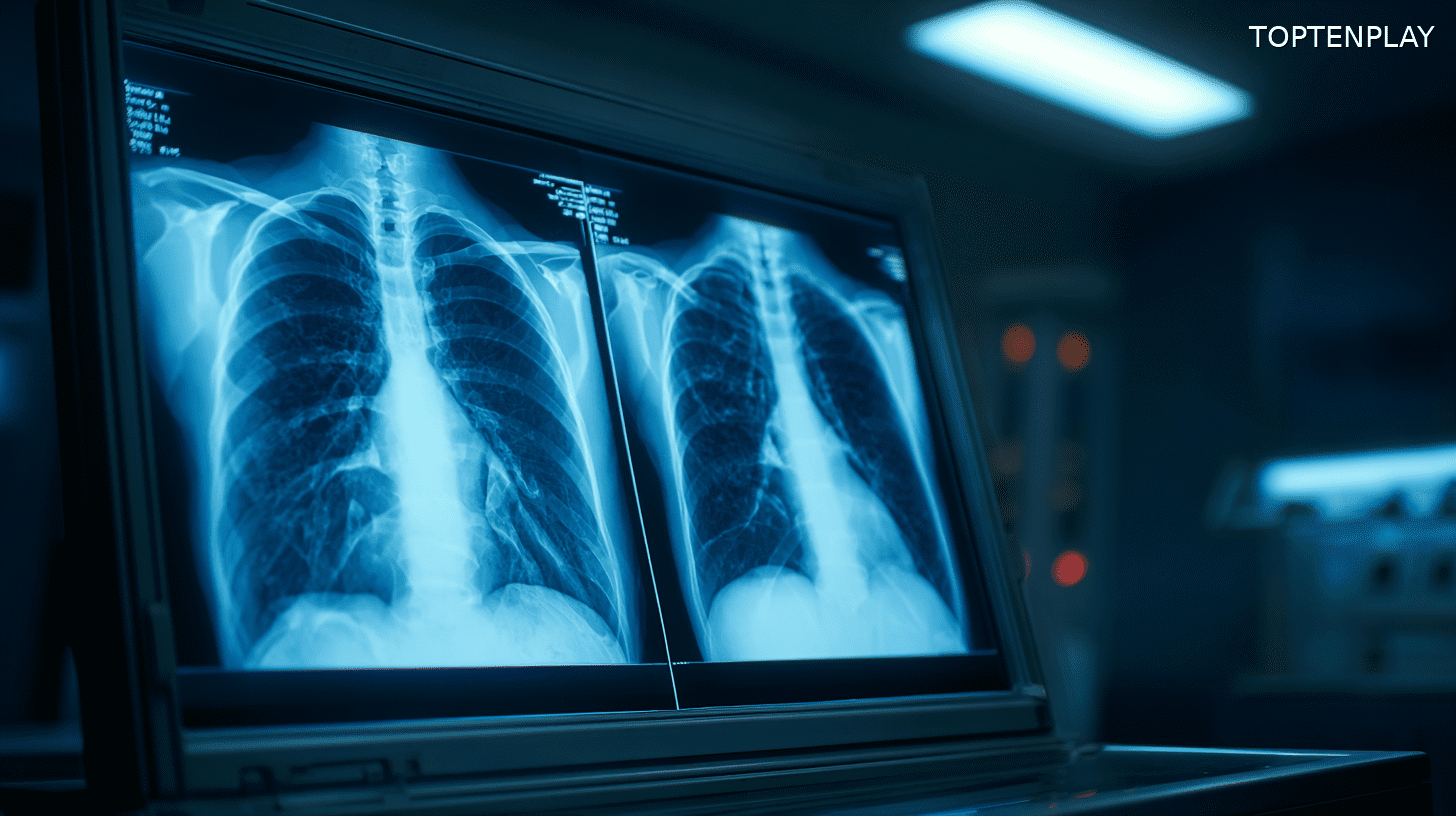

L’ambulance, les examens médicaux, puis la révélation. Ce que Cloey pensait être une crise cardiaque révèle une réalité autrement plus inquiétante. Les médecins livrent un diagnostic qui la glace d’effroi : son poumon gauche présente une poche d’huile, et ses deux organes respiratoires baignent dans une substance visqueuse.

« Autour de mes deux poumons il y avait de l’huile. C’était terrifiant d’entendre ça », confie la jeune femme, encore sous le choc. Les praticiens lui expliquent alors le processus destructeur : « C’est l’huile de la vape qui s’épaissit quand vous tirez dessus et s’attache à vos poumons ».

Le verdict médical tombe comme un couperet : pneumonie lipoïde, plus communément appelée « popcorn lung ». Cette pathologie résulte de l’accumulation progressive de substances huileuses dans les alvéoles pulmonaires, provoquant inflammations et lésions irréversibles. « Techniquement, à ce moment-là, j’avais un popcorn lung. C’est comme ça qu’ils l’appellent ici », raconte Cloey.